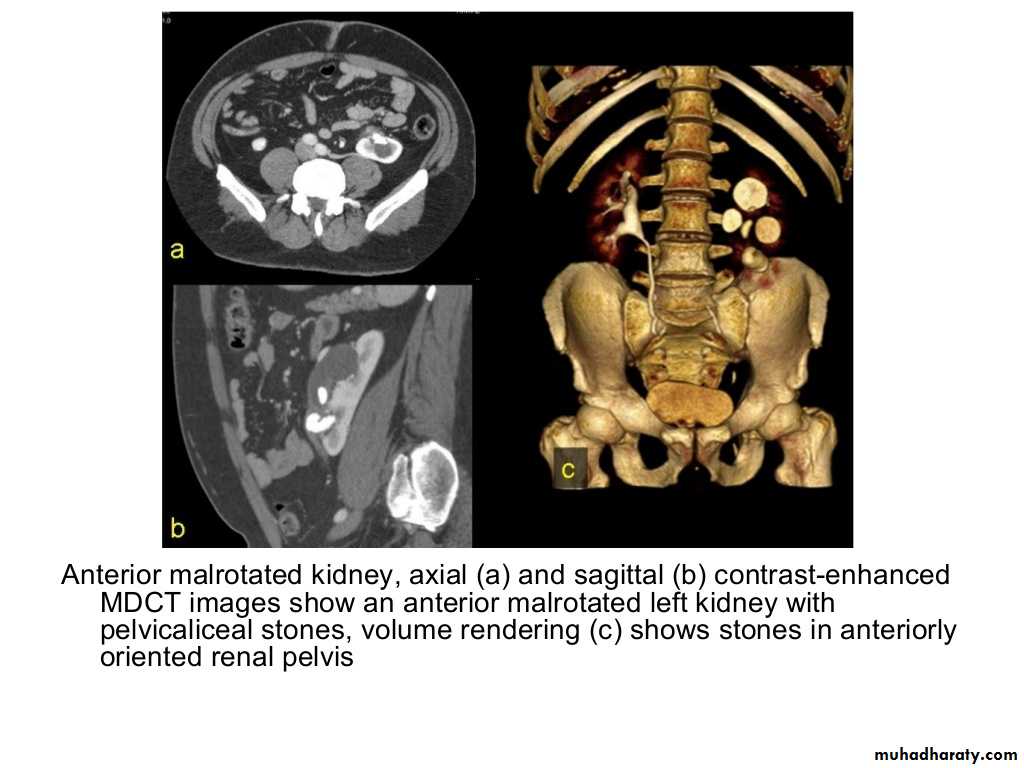

IVU shows

1. The kidneys at low position .2.Close to the spine with long axis parallel to the spine

3. Malrotation manifested by medially directed calyces.

4- The renal pelvis and ureters are anterior and lateral in position.

5- Hydronephrosis and calculi highly associated.